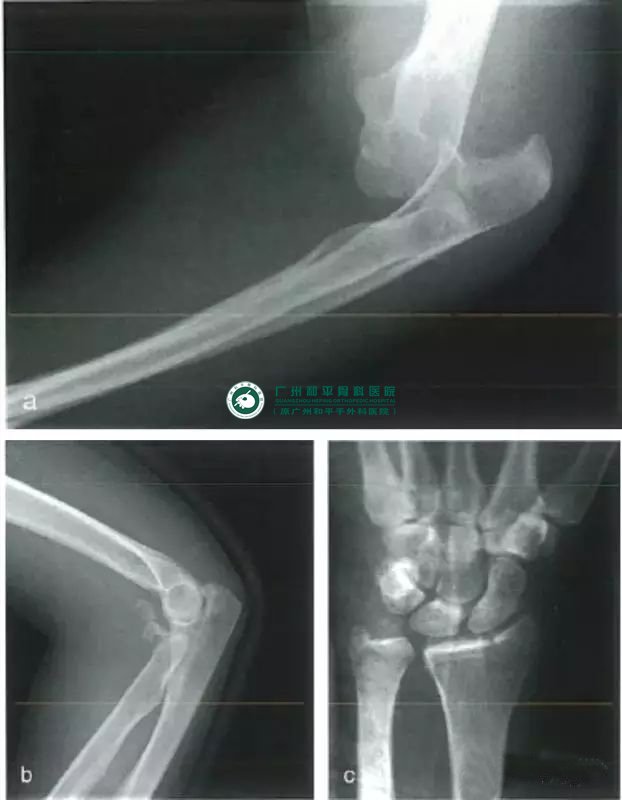

Essex-Lopresti损伤

这种复杂的损伤涉及肘关节骨折脱位合并桡骨远端骨折或下尺桡关节脱位。桡骨骨干有多段骨折或呈“漂浮”状态。如果合并上、下尺桡关节同时脱位,可导致严重的功能障碍。用于治疗孟氏损伤与盖氏损伤的固定技术同样适用于治疗这种损伤。

a、复位前的侧位片;b、复位后的侧位片;c、尺侧正常的腕关节,桡骨头损伤导致桡骨短缩